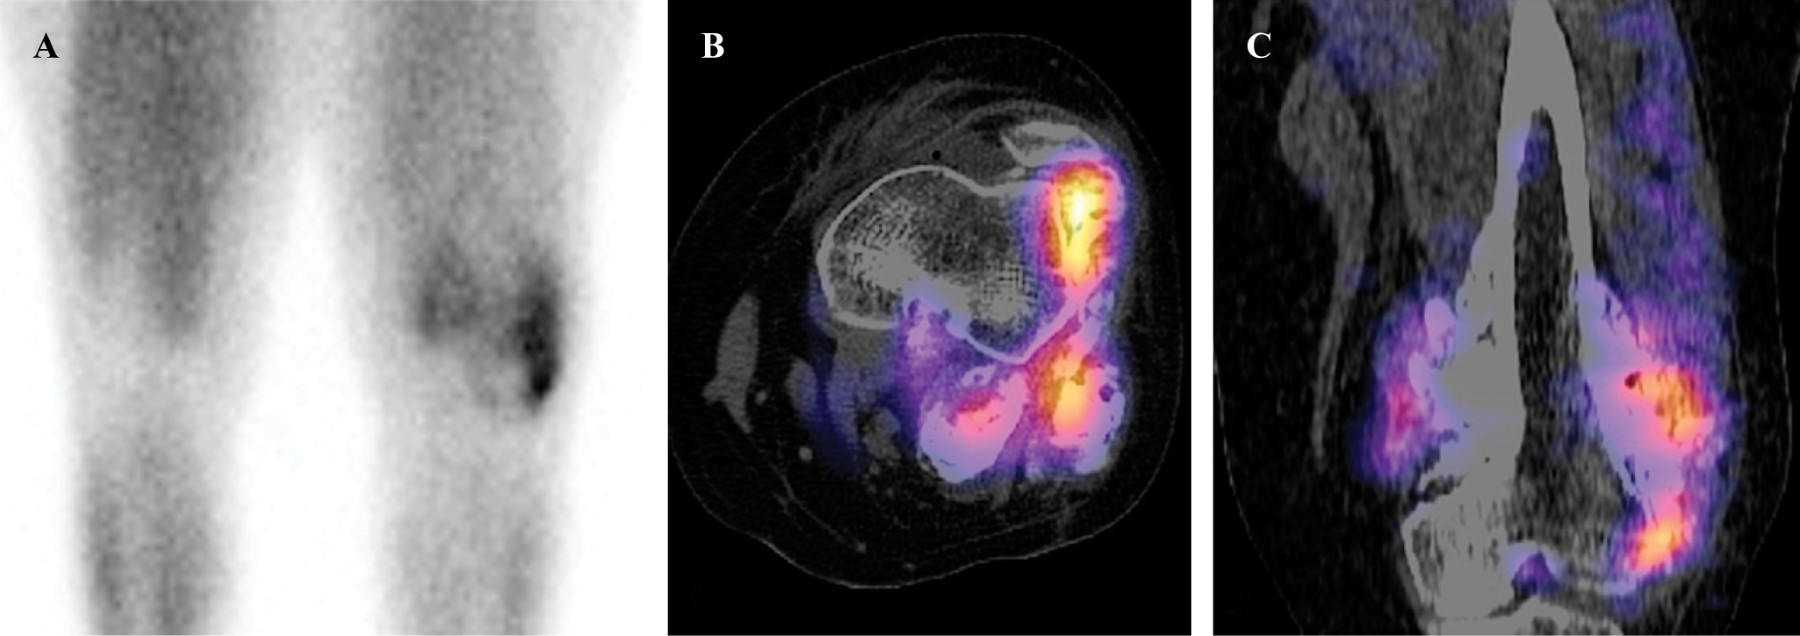

Introducción: el osteosarcoma parosteal convencional es un tumor óseo maligno poco común, que comprende el 4% de todos los osteosarcomas. Aunque es poco común, el osteosarcoma parosteal es el tipo más común de osteosarcoma de la superficie ósea. Presentamos las características clínicas, histológicas y de imagen de una variante histológica rara de un osteosarcoma parosteal, revisamos la literatura y enfatizamos la importancia de la correlación radio-patológica, así como la interpretación de una biopsia representativa para obtener el diagnóstico correcto. Reporte de caso: mujer de 36 años inició su cuadro un año antes de su ingreso al hospital con aumento de volumen en rodilla izquierda y dolor. Los estudios de imagen mostraron una tumoración heterogénea yuxtacortical localizada en la superficie posterior de la metáfisis femoral distal. Se realizó biopsia incisional, con diagnóstico de osteosarcoma parosteal y se realizó resección quirúrgica amplia. De acuerdo con los hallazgos de la pieza quirúrgica se realizó el diagnóstico de osteosarcoma parosteal con componentes de condrosarcoma y liposarcoma de bajo grado. El conocimiento de esta rara variante de osteosarcoma parosteal puede llevar a los ortopedistas oncólogos a considerar otros componentes y proporcionar márgenes quirúrgicos adecuados. Conclusión: presentamos las características clínicas, histológicas y de imagen de un osteosarcoma parosteal con componentes de liposarcoma y condrosarcoma de bajo grado.

Figura 1